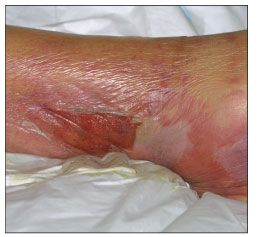

Cellulitis and erysipelasS aureus and S pyogenes are often implicated in cellulitis and erysipelas. Although all age groups are affected, older persons are at higher risk for these infections. Erythema, pain, swelling, and warmth are common symptoms. Fever-if only low-grade-also may be present. Cellulitis (Figure 3), which typically affects the lower legs, involves the subcutaneous fat and is often less well demarcated than erysipelas, which affects the skin of the lower extremities (Figures 4 and 5) and, less often, the facial area (Figure 6).

Figure 3 – This example of cellulitis shows inflammation, blistering, and possible lymphatic involvement. (Photo courtesy of Noah S. Scheinfeld, MD, JD.)

Clindamycin, trimethoprim/sulfamethoxazole, and doxycycline are being recommended by the Infectious Diseases Society of America for treatment of cellulitis with purulent drainage or similar skin and soft tissue infections caused by S aureus (assumed to be methicillin-resistant and treated empirically).2 An agent that has activity against β-hemolytic streptococci is recommended for cellulitis in which streptococcal involvement is suspected.2 Nafcillin or cefazolin is recommended for streptococcal cellulitis, and penicillin or a cephalosporin is the first-line treatment for streptococcal erysipelas. Substitutes in persons with penicillin allergy are vancomycin and clindamycin.3